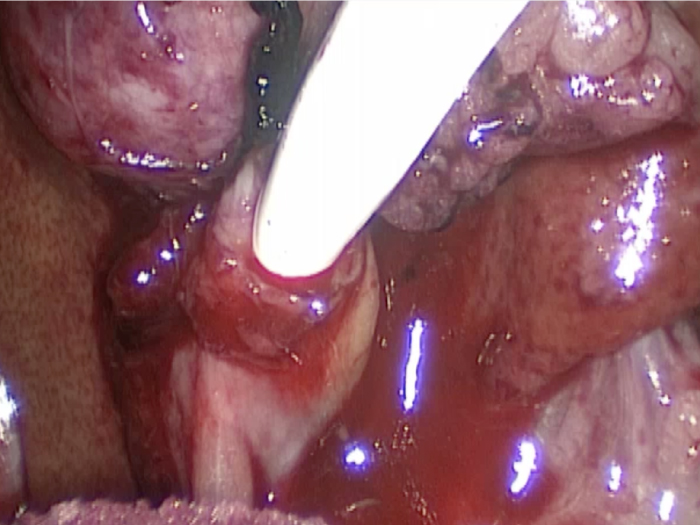

胆嚢が破裂した様子を腹腔内にカメラを入れて観察した像です。

胆嚢から漏れ出た胆汁が腹腔内に確認できます